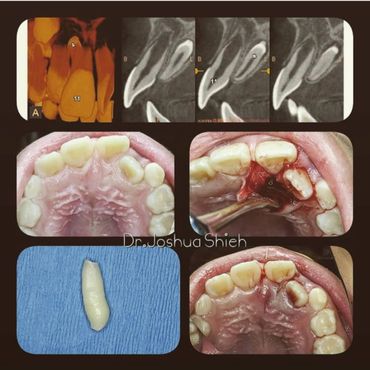

If the tooth is planned for extraction, an x-ray of the area will be taken to plan for the type of extraction.

Surgical Dental Extraction

A surgical extraction is a more complex procedure. It is used if a tooth may have broken off at the gum line or has not come into the mouth yet. Surgical extractions are commonly performed by general dentists or oral surgeons depending on the case. Sometimes it’s necessary to remove some of the bone around the tooth or to cut the tooth in half in order to extract it. For surgical extractions, patients receive local anesthetic. A suture is usually required to control bleeding and facilitate healing.